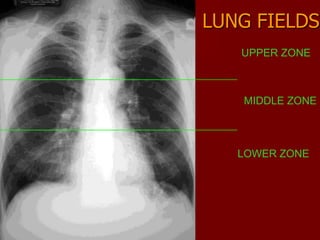

LUNG FIELDS

UPPER ZONE

MIDDLE ZONE

LOWER ZONE